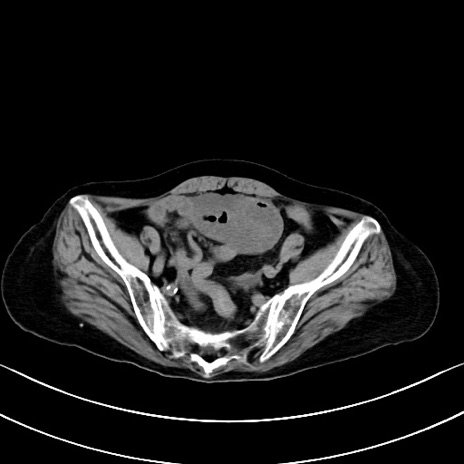

横断像